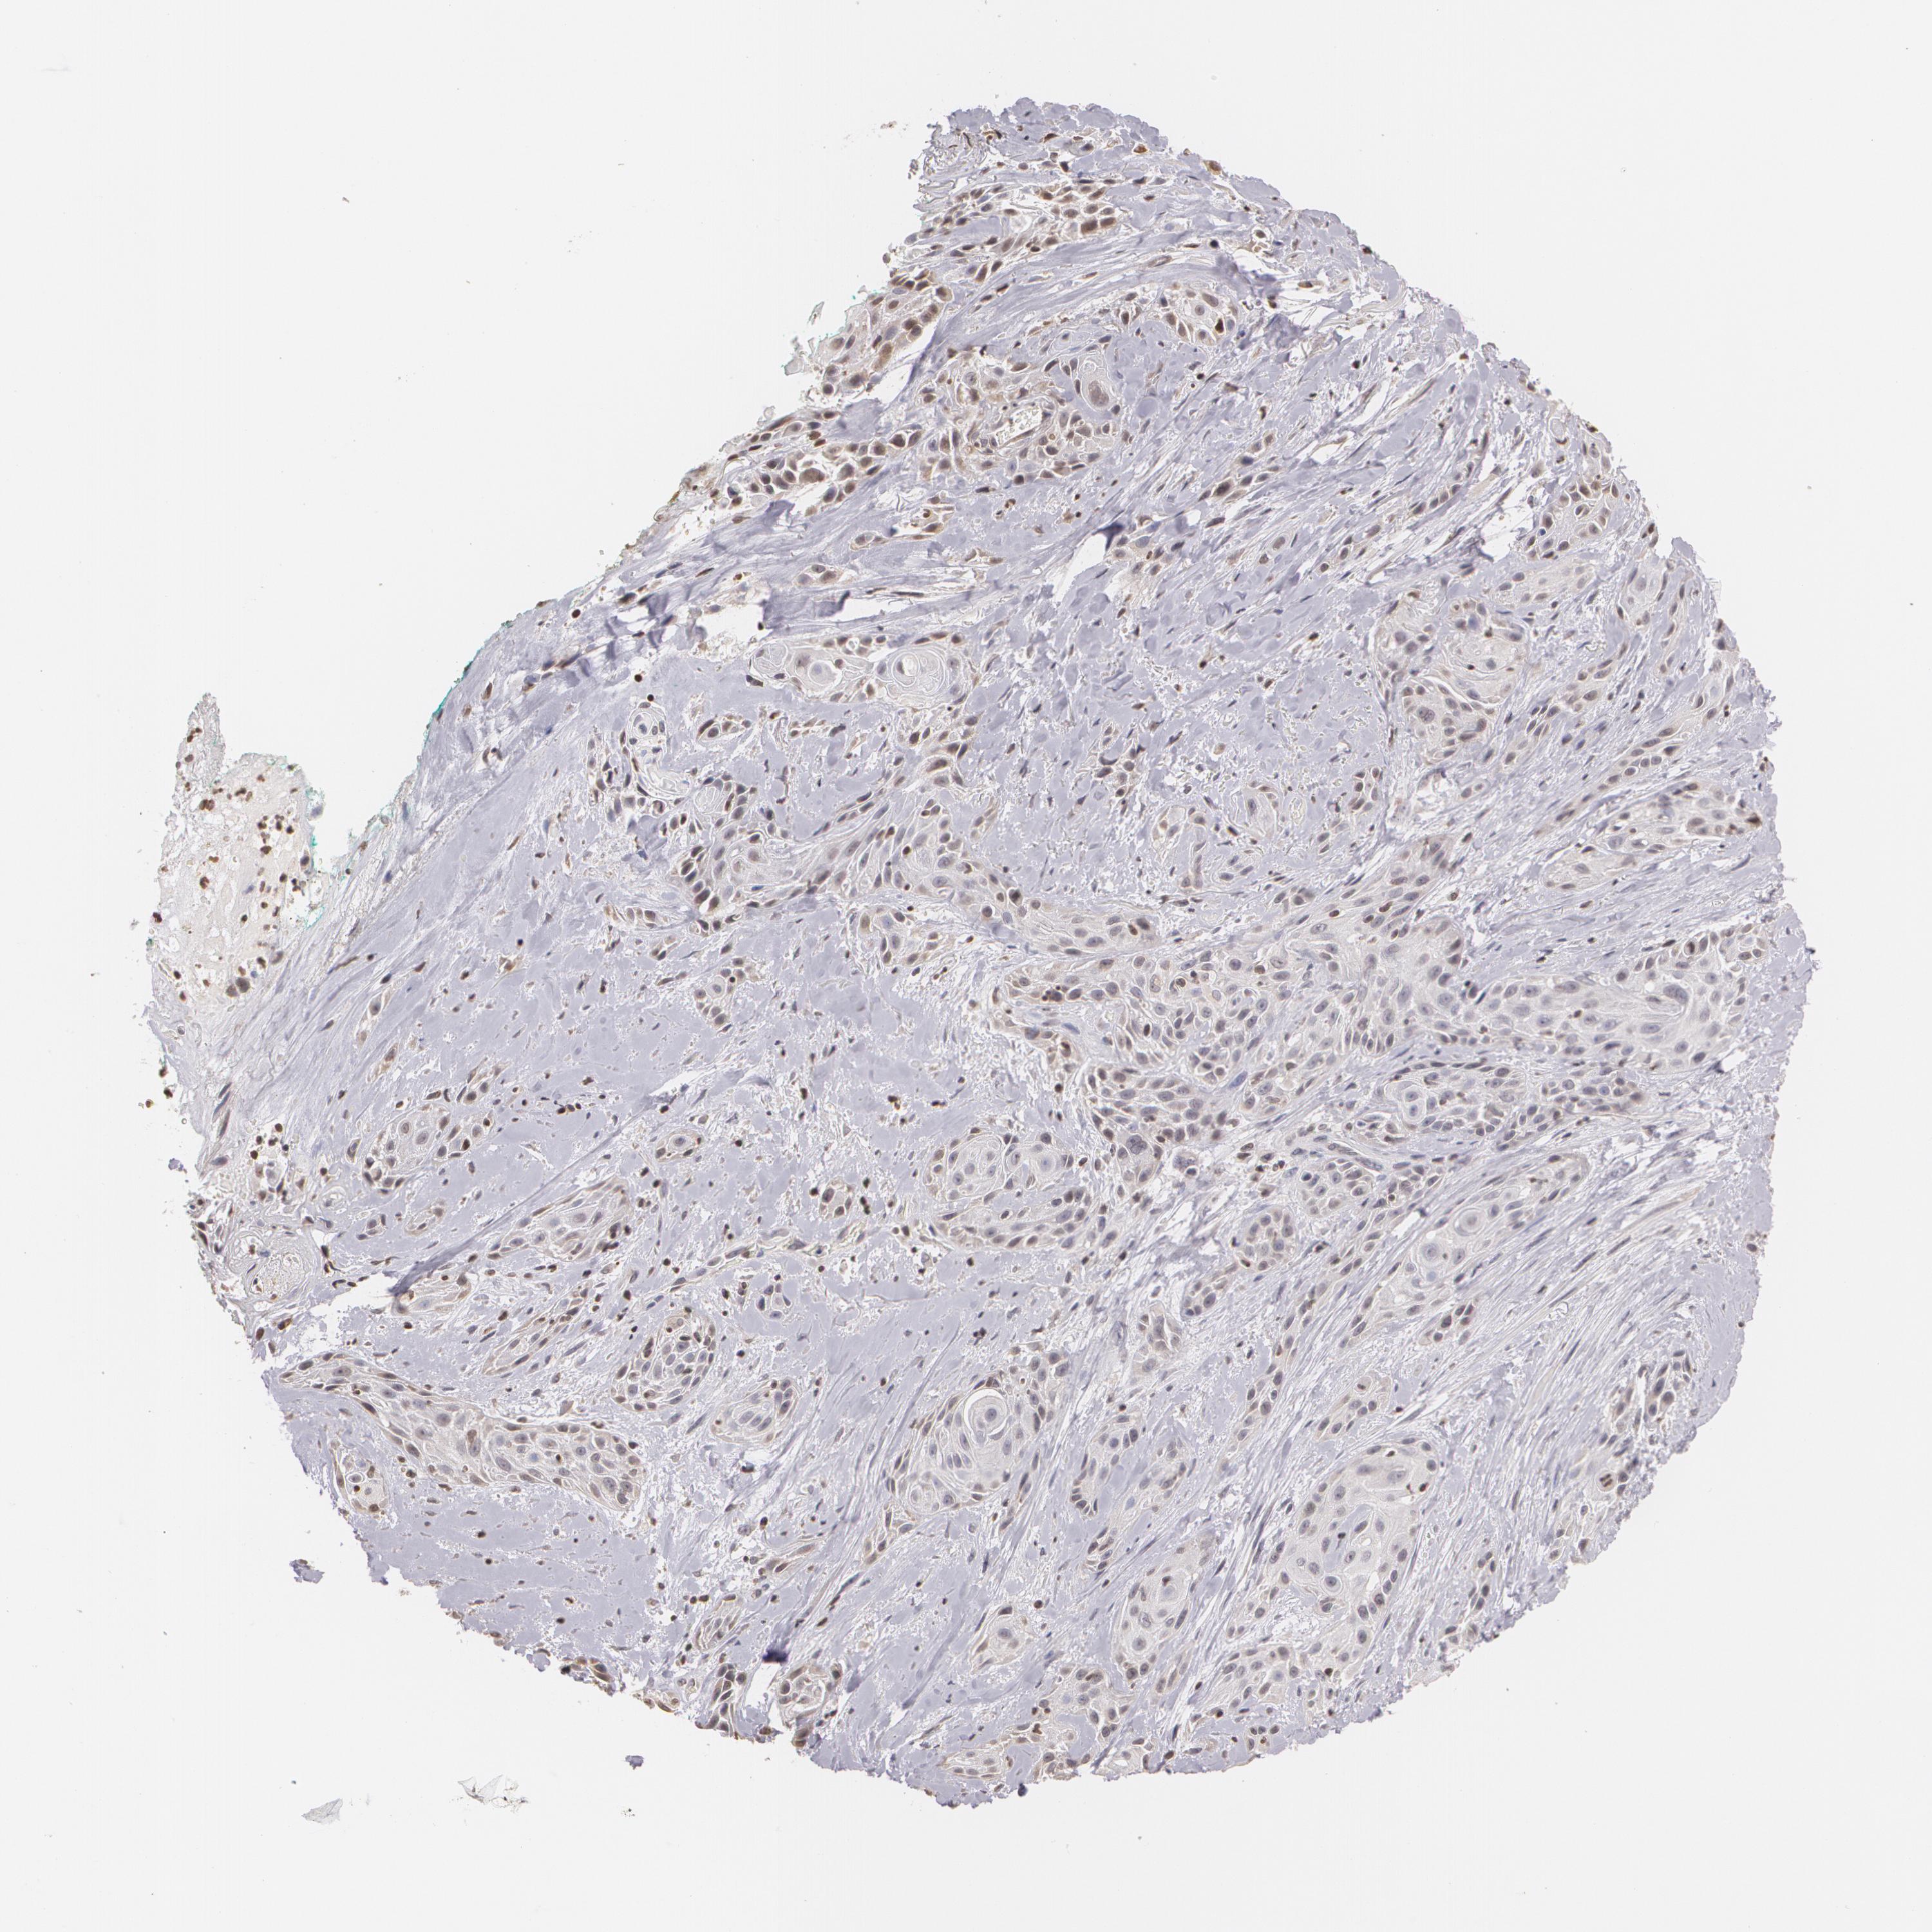

SKIN CANCER - Protein expressioni

A mouse-over function shows sample information and annotation data. Click on an image to view it in a full screen mode. Samples can be filtered based on level of antibody staining by selecting one or several of the following categories: high, medium, low and not detected. The assay and annotation is described here.

Antibody stainingi

Antibody staining in the annotated cell types in the current human tissue is reported as not detected, low, medium, or high, based on conventional immunohistochemistry profiling in selected tissues. This score is based on the combination of the staining intensity and fraction of stained cells.

Each image is clickable and will lead to virtual microscopy that enables deeper exploration of all samples and also displays staining intensity scores, fraction scores and subcellular localization as well as patient and tissue information for each sample.

Antibody CAB002008

Antibody CAB002009

Staining

High

Medium

Low

Not detected

Intensity

Strong

Moderate

Weak

Negative

Quantity

>75%

75%-25%

<25%

None

Location

Nuclear

Cytoplasmic/membranous

Cytoplasmic/membranous,nuclear

Squamous cell carcinoma, NOS

Basal cell carcinoma